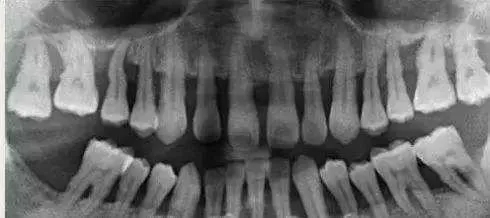

2、牙龈炎没有骨的破坏,所以X线片上没有骨吸收的情况。而牙周炎X线片上可见牙槽嵴的高度降低,呈水平型吸收,也可出现近牙根面的牙槽骨吸收,呈垂直或角形骨吸收,这种骨的吸收,临床上表现为骨下袋。

640.webp (4).jpg